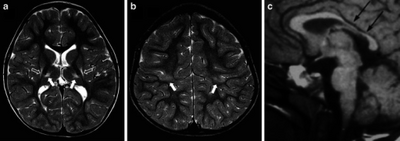

MR images in a boy with dyskinetic cerebral palsy who has neuroimaging findings of acute profound hypoxic–ischaemic brain injury

Around 70% of patients with DCP show lesions in the cortical and deep grey matter of the brain, more specifically in the basal ganglia and thalamus. However, other brain lesions and even normal-appearing MRI findings can occur, for example white matter lesions and brain maldevelopments.[3][15][17][18] Patients with pure basal ganglia and thalamus lesions are more likely to show more severe choreoathetosis whereas dystonia may be associated with other brain lesions, such as the cerebellum.[3] These lesions occur mostly during the peri- and postnatal period since these regions have a high vulnerability during the late third trimester of the pregnancy.[19] Unfortunately, contemporary imaging is not sophisticated enough to detect all subtle brain deformities and network disorders in dystonia. Research with more refined imaging techniques including diffusion tensor imaging and functional MRI is required.[8][20]